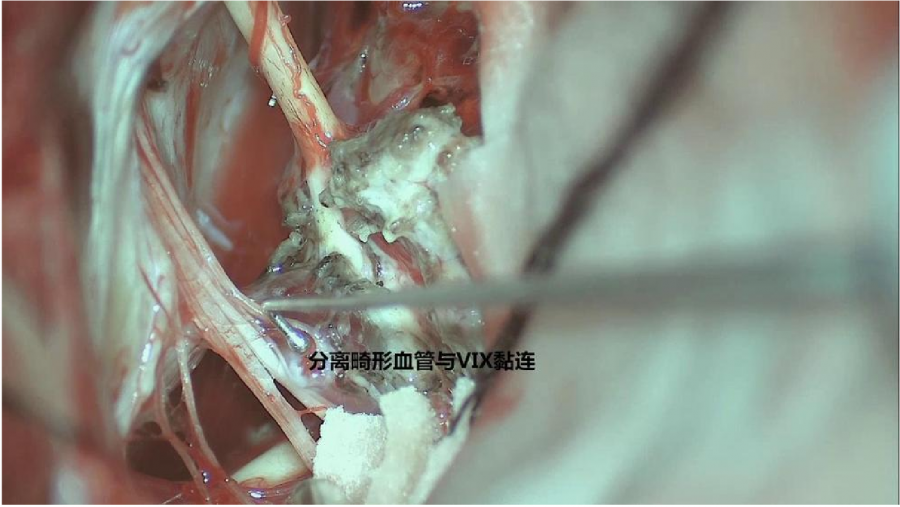

⾏左侧远外侧⼊路脑⼲⾎管畸形切除术,术中所⻅:

3、脑⼲动静脉畸形⼿术切除是注意辨别供⾎动脉与引流静脉,其往往不似其他部位的动静 脉畸形,有叫粗⼤的引流静脉。术中如果不能辨清各⾎管来源与去处,往往会造成不可估量的损失。